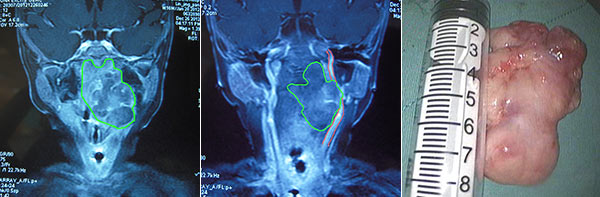

由于孩子症状日益严重,还出现了呼吸极度困难而导致的胸骨上窝、锁骨上窝、肋间隙出现明显凹陷的“三凹征”,为能让孩子呼吸,当地医院先予以气管切开治疗。经行颈部MR检查显示:在涛涛的咽喉旁竟有个的巨大肿瘤,大小约7*4cm,差不多半根香蕉大小!上至颅底水平,下至喉水平。而且肿瘤外侧将紧贴并向外推移颈部大血管,挤压口咽部,几乎到令患儿窒息的程度!

左:咽旁、咽后间隙的巨大肿瘤;中:肿瘤压迫大血管;右:切除的肿瘤

持续了1小时的手术十分成功,术后5天就封闭了气管套管,第7天拔除气管套管,术后复查MR未见肿瘤残余。涛涛恢复良好,很快就恢复了可人的模样,全家人悬着的心终于放了下来。